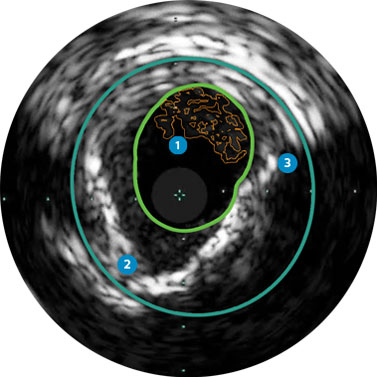

Lumen

Eccentric fibrotic plaque with deep calcium nodule

Acoustic shadowing

Vessel size: 5.5 mm diameter Plaque morphology: Fibrotic plaque with intimal and medial calcium Plaque geometry: Eccentric lesion Guidewire position: True lumen